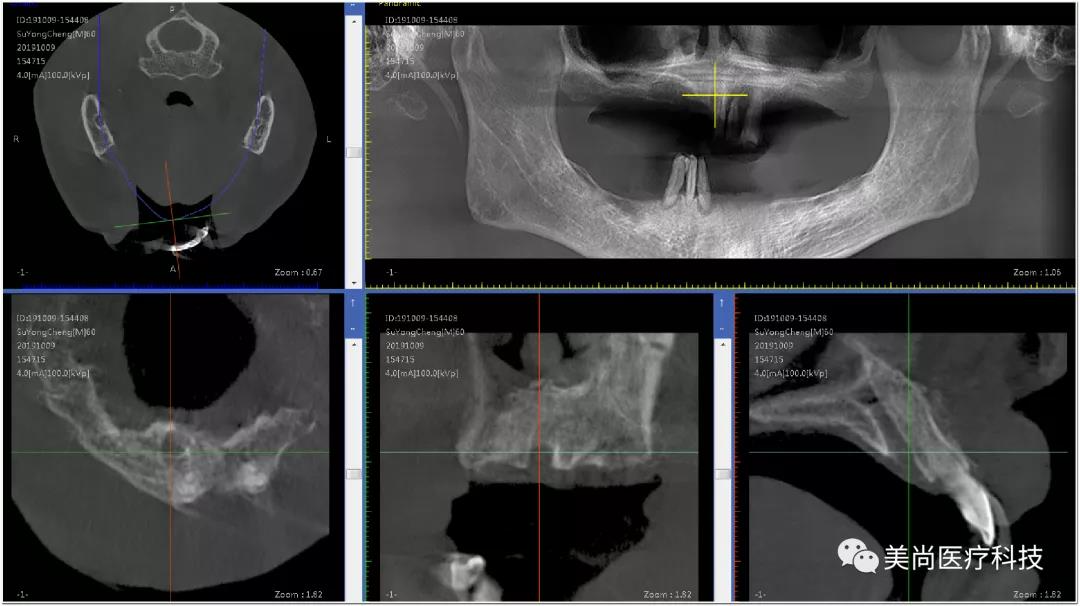

术前X-ray